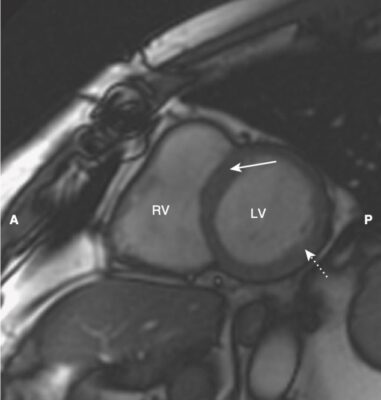

- Một trong những lợi ích của MRI là hình ảnh của nó có thể được hiển thị ở bất kỳ mặt phẳng nào. Bên cạnh các mặt phẳng cắt ngang (axial), đứng dọc (sagittal) và đứng bên (coronal, trán), có một số góc nhìn đặc hiệu thường được sử dụng trong MRI tim cho phép hình dung rõ nhất về tim. Chúng được gọi là trục dài cắt ngang (còn được gọi là mặt cắt bốn buồng), trục dài thẳng đứng, trục ngắn và mặt cắt ba buồng.

- Cấu trúc giải phẫu của tim trong các mặt phẳng cắt ngang, đứng dọc và trán giống như được thấy trên CT (Hình 16).

- Mặt cắt trục dài cắt ngang (bốn buồng) giống hình cắt ngang và được sử dụng tốt nhất để đánh giá vách ngăn và thành bên và đỉnh của tâm thất trái, thành tự do của tâm thất phải và kích thước của các buồng tim. Các van hai lá và van ba lá đặc biệt nhìn rõ ràng trong hình ảnh này (Hình 17).

- Lát cắt trục ngắn mô tả tâm thất trái và phải để thực hiện các đo lường thể tích (Hình 19).